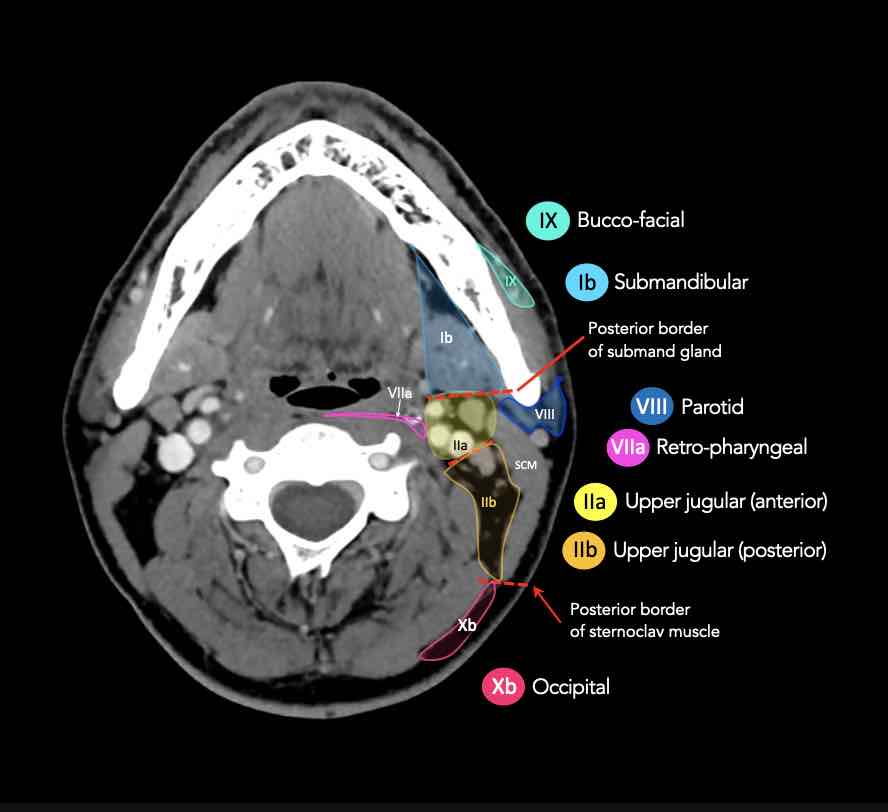

CT Scan Mặt Cắt Ngang (Axial CT)

Các lát cắt CT mặt phẳng ngang tương ứng với hình minh họa tổng quan.

Các lát cắt CT mặt phẳng ngang với hình ảnh chi tiết hơn.

Nhấp vào hình ảnh để phóng to.

Tầng II có thể được chia thành tầng IIa và tầng IIb bằng cách vẽ một đường tại bờ sau của tĩnh mạch cảnh trong.

Các hạch bạch huyết ở tầng IIa và IIb có nguy cơ chứa di căn từ các ung thư hốc mũi và khoang miệng, vòm hầu, hầu miệng, hạ hầu, thanh quản và các tuyến nước bọt lớn.

Tầng IIb thường liên quan hơn đến các khối u nguyên phát ở hầu miệng hoặc vòm hầu, và ít thường xuyên hơn với các khối u ở khoang miệng, thanh quản hoặc hạ hầu [1].